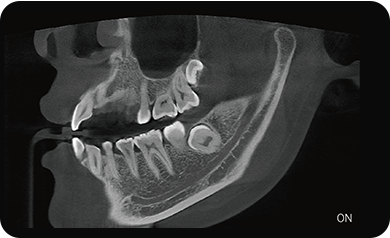

超能去伪 至臻影像

临床样片